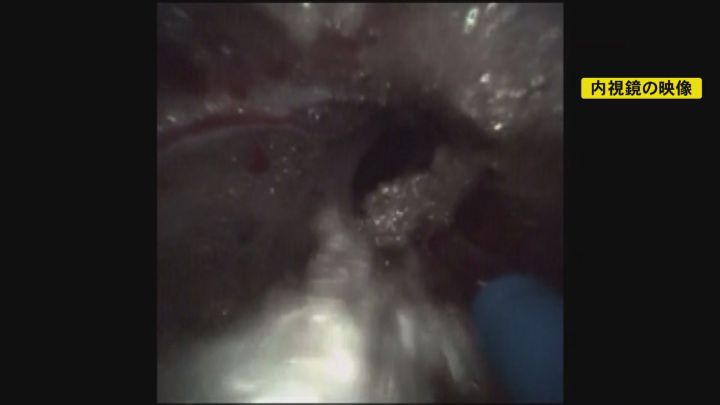

カテーテルには2種類の医療器具を通します。黒が内視鏡で、青がヘルニアを除去するレーザー装置、共に直径は1ミリほどです。

内視鏡が映した映像には、“癒着”で炎症が起こることで生じた、白っぽい綿毛のようが映っています。

神経を傷つけないように、ヘルニアと一緒にレーザーで焼いて、除去していきます。

レーザー装置を慎重に細かく動かしていくと、きれいになっていくのが分かります。